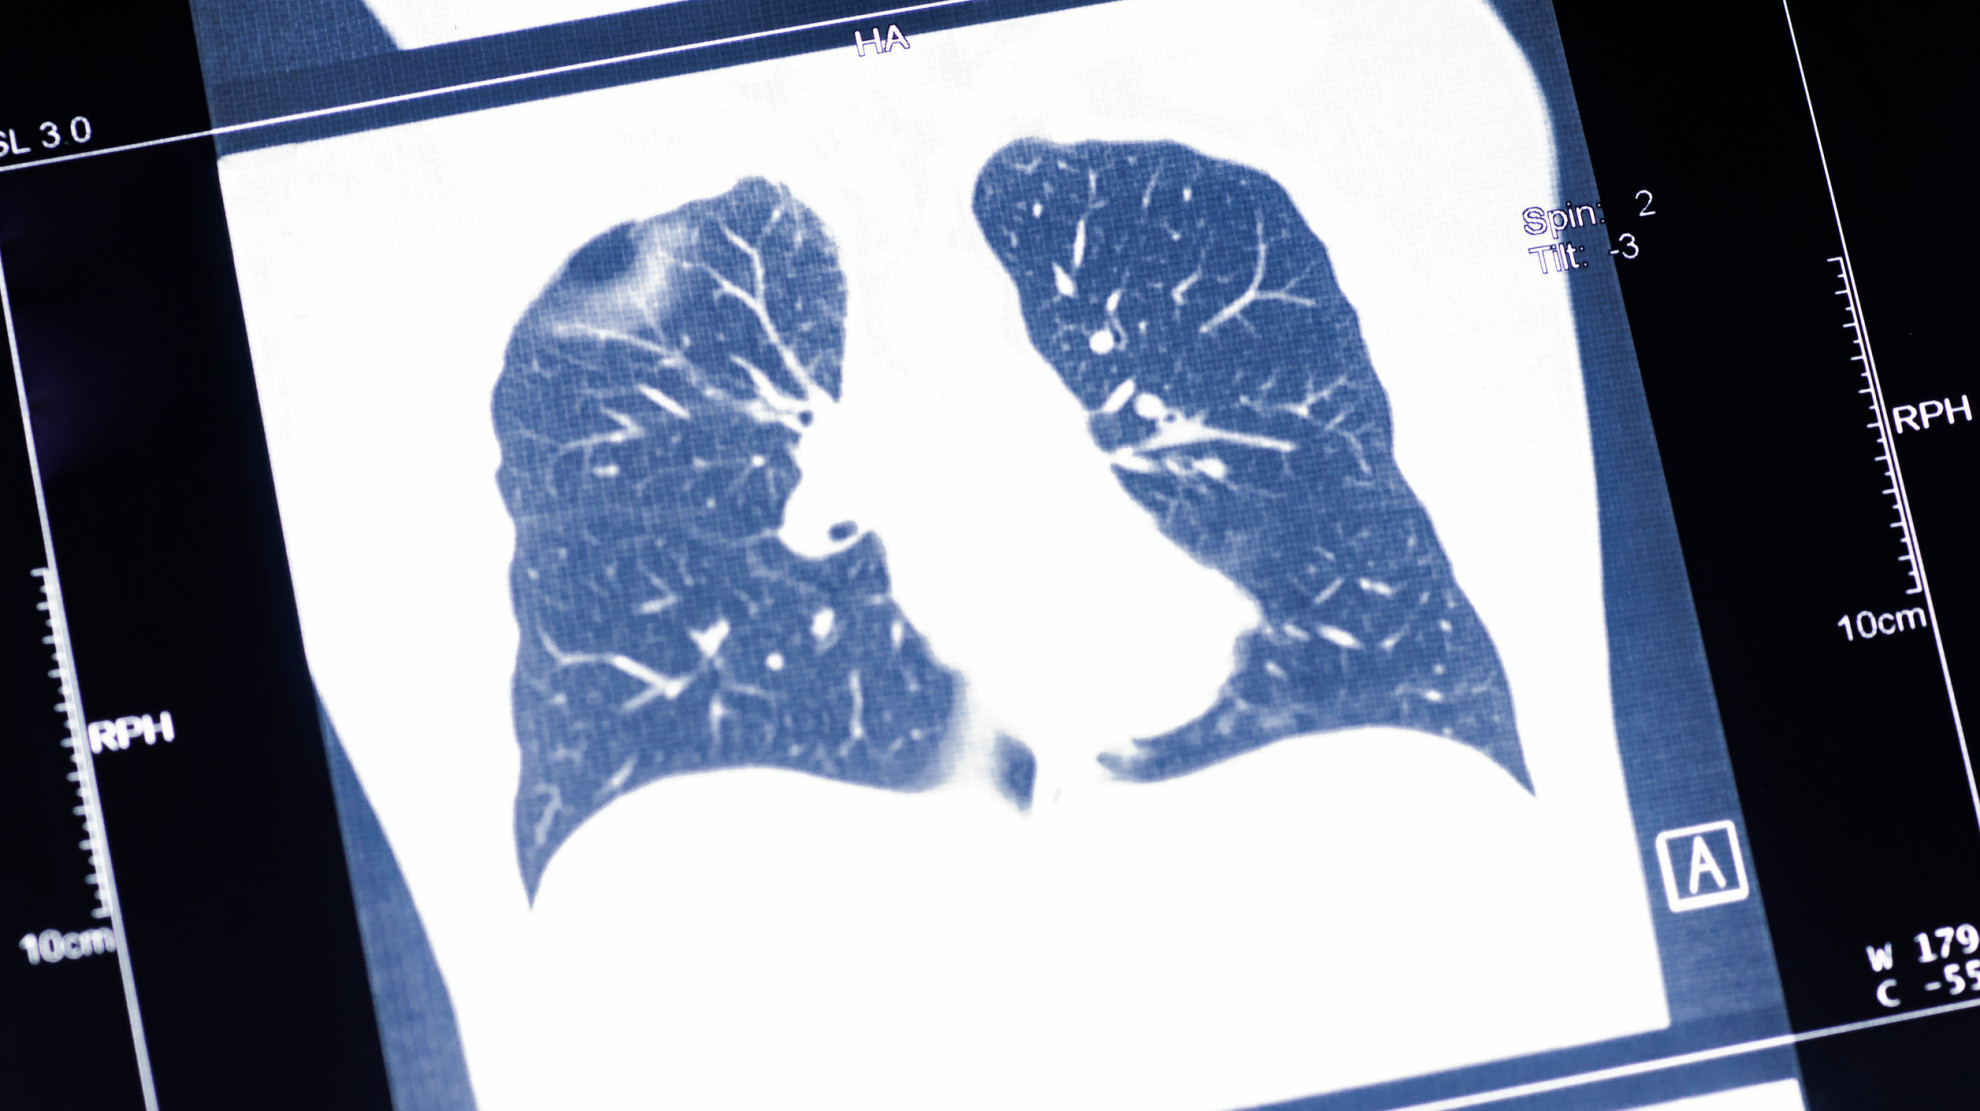

Скрининг РЛ — это активный поиск заболевания у лиц без симптомов, но с повышенным риском, прежде всего — у курильщиков с большим стажем. Для диагностики рака легкого могут использоваться разные подходы: рентгенография грудной клетки, цитологическое исследование мокроты, МРТ, компьютерная томография, флюорография. В России наиболее распространенным методом является рентгенография. Однако наилучшее соотношение чувствительности и специфичности для раннего выявления РЛ показала низкодозная компьютерная томография (НДКТ).

НДКТ позволяет обнаруживать небольшие узлы, которые незаметны на рентгенограммах, за счет лучшего пространственного разрешения и трехмерной реконструкции. Согласно исследованию, опубликованному в журнале «Вестник рентгенологии и радиологии», внедрение в НДКТ вместо рентгенографии в диспансеризацию позволит увеличить выявляемость РЛ на ранних стадиях в 5,37 раза.